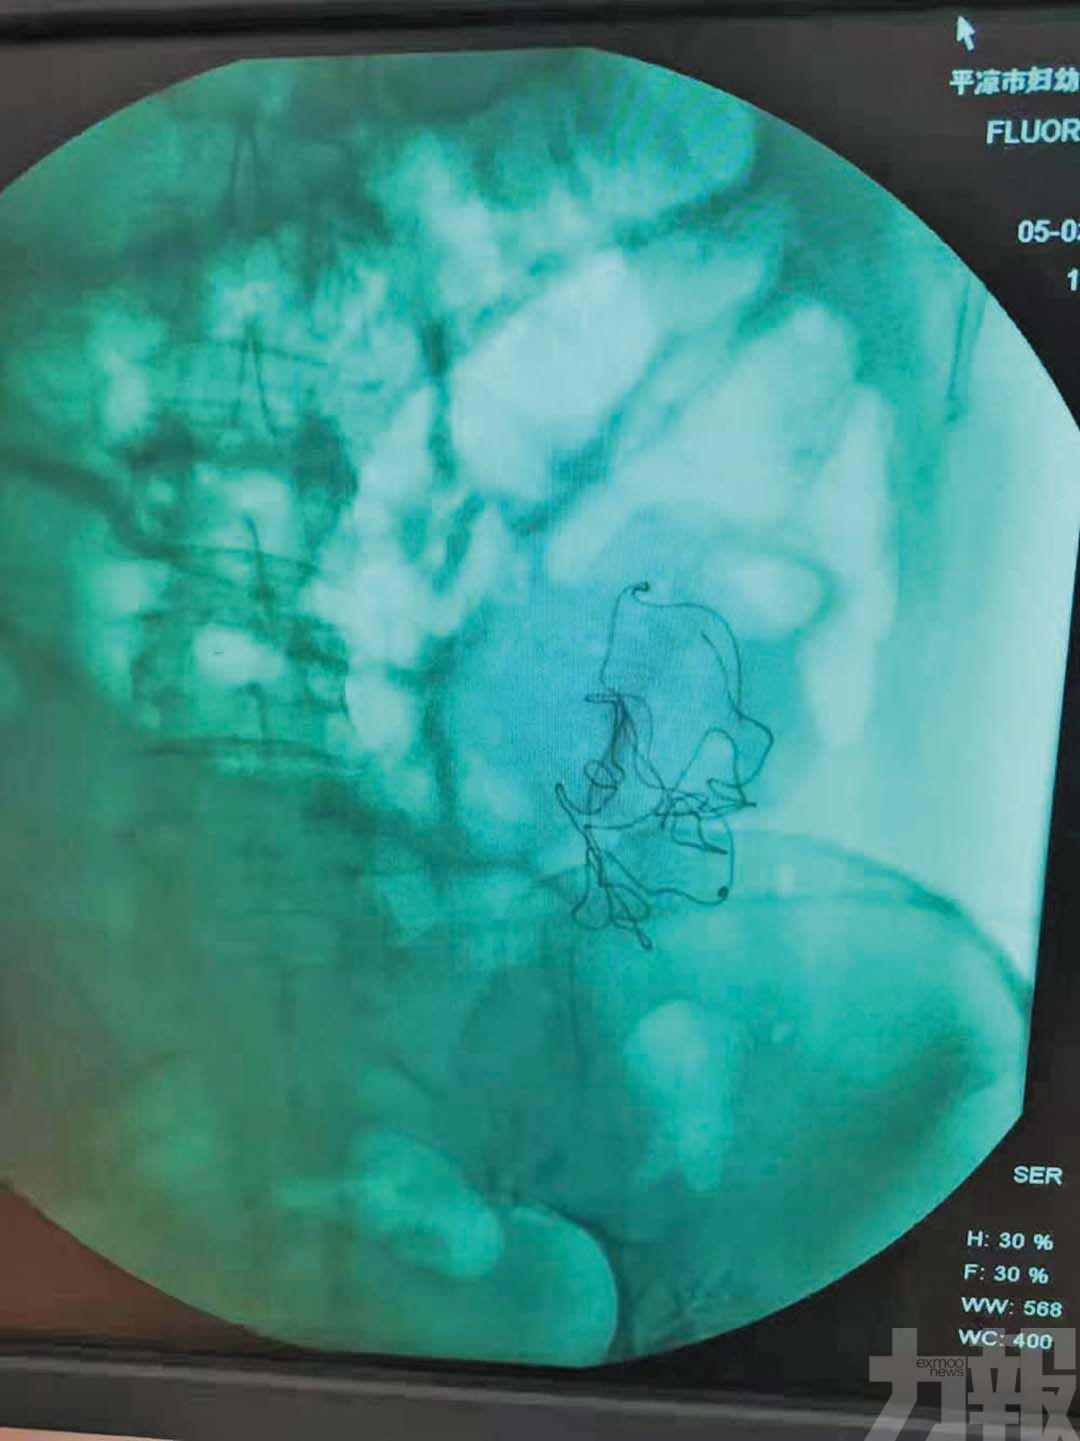

秦紅利分娩後,進行X光檢查發現異物清晰可見。(網絡圖片)

除新生兒情況外,秦紅利本人亦被指在未經知情同意下接受第二次開腹手術。她回憶稱,當時醫護人員在產房內曾反覆尋找一塊遺失紗布,其後安排X光檢查,並在未簽署任何文件情況下將其送入手術室。她表示,在手術過程中曾看到醫生從腹腔取出帶血紗布,懷疑該物曾被遺留體內。

更早於2025年7月,當地衛健部門已查明,涉事醫生在病歷中偽造手術記錄及術後病程記錄,包括虛構「 X光顯示少量液平面 」等內容,而影像中顯示的腹腔異物並未在正式記錄中反映。對於是否曾將紗布遺留患者體內,院方至今未有一致說法。